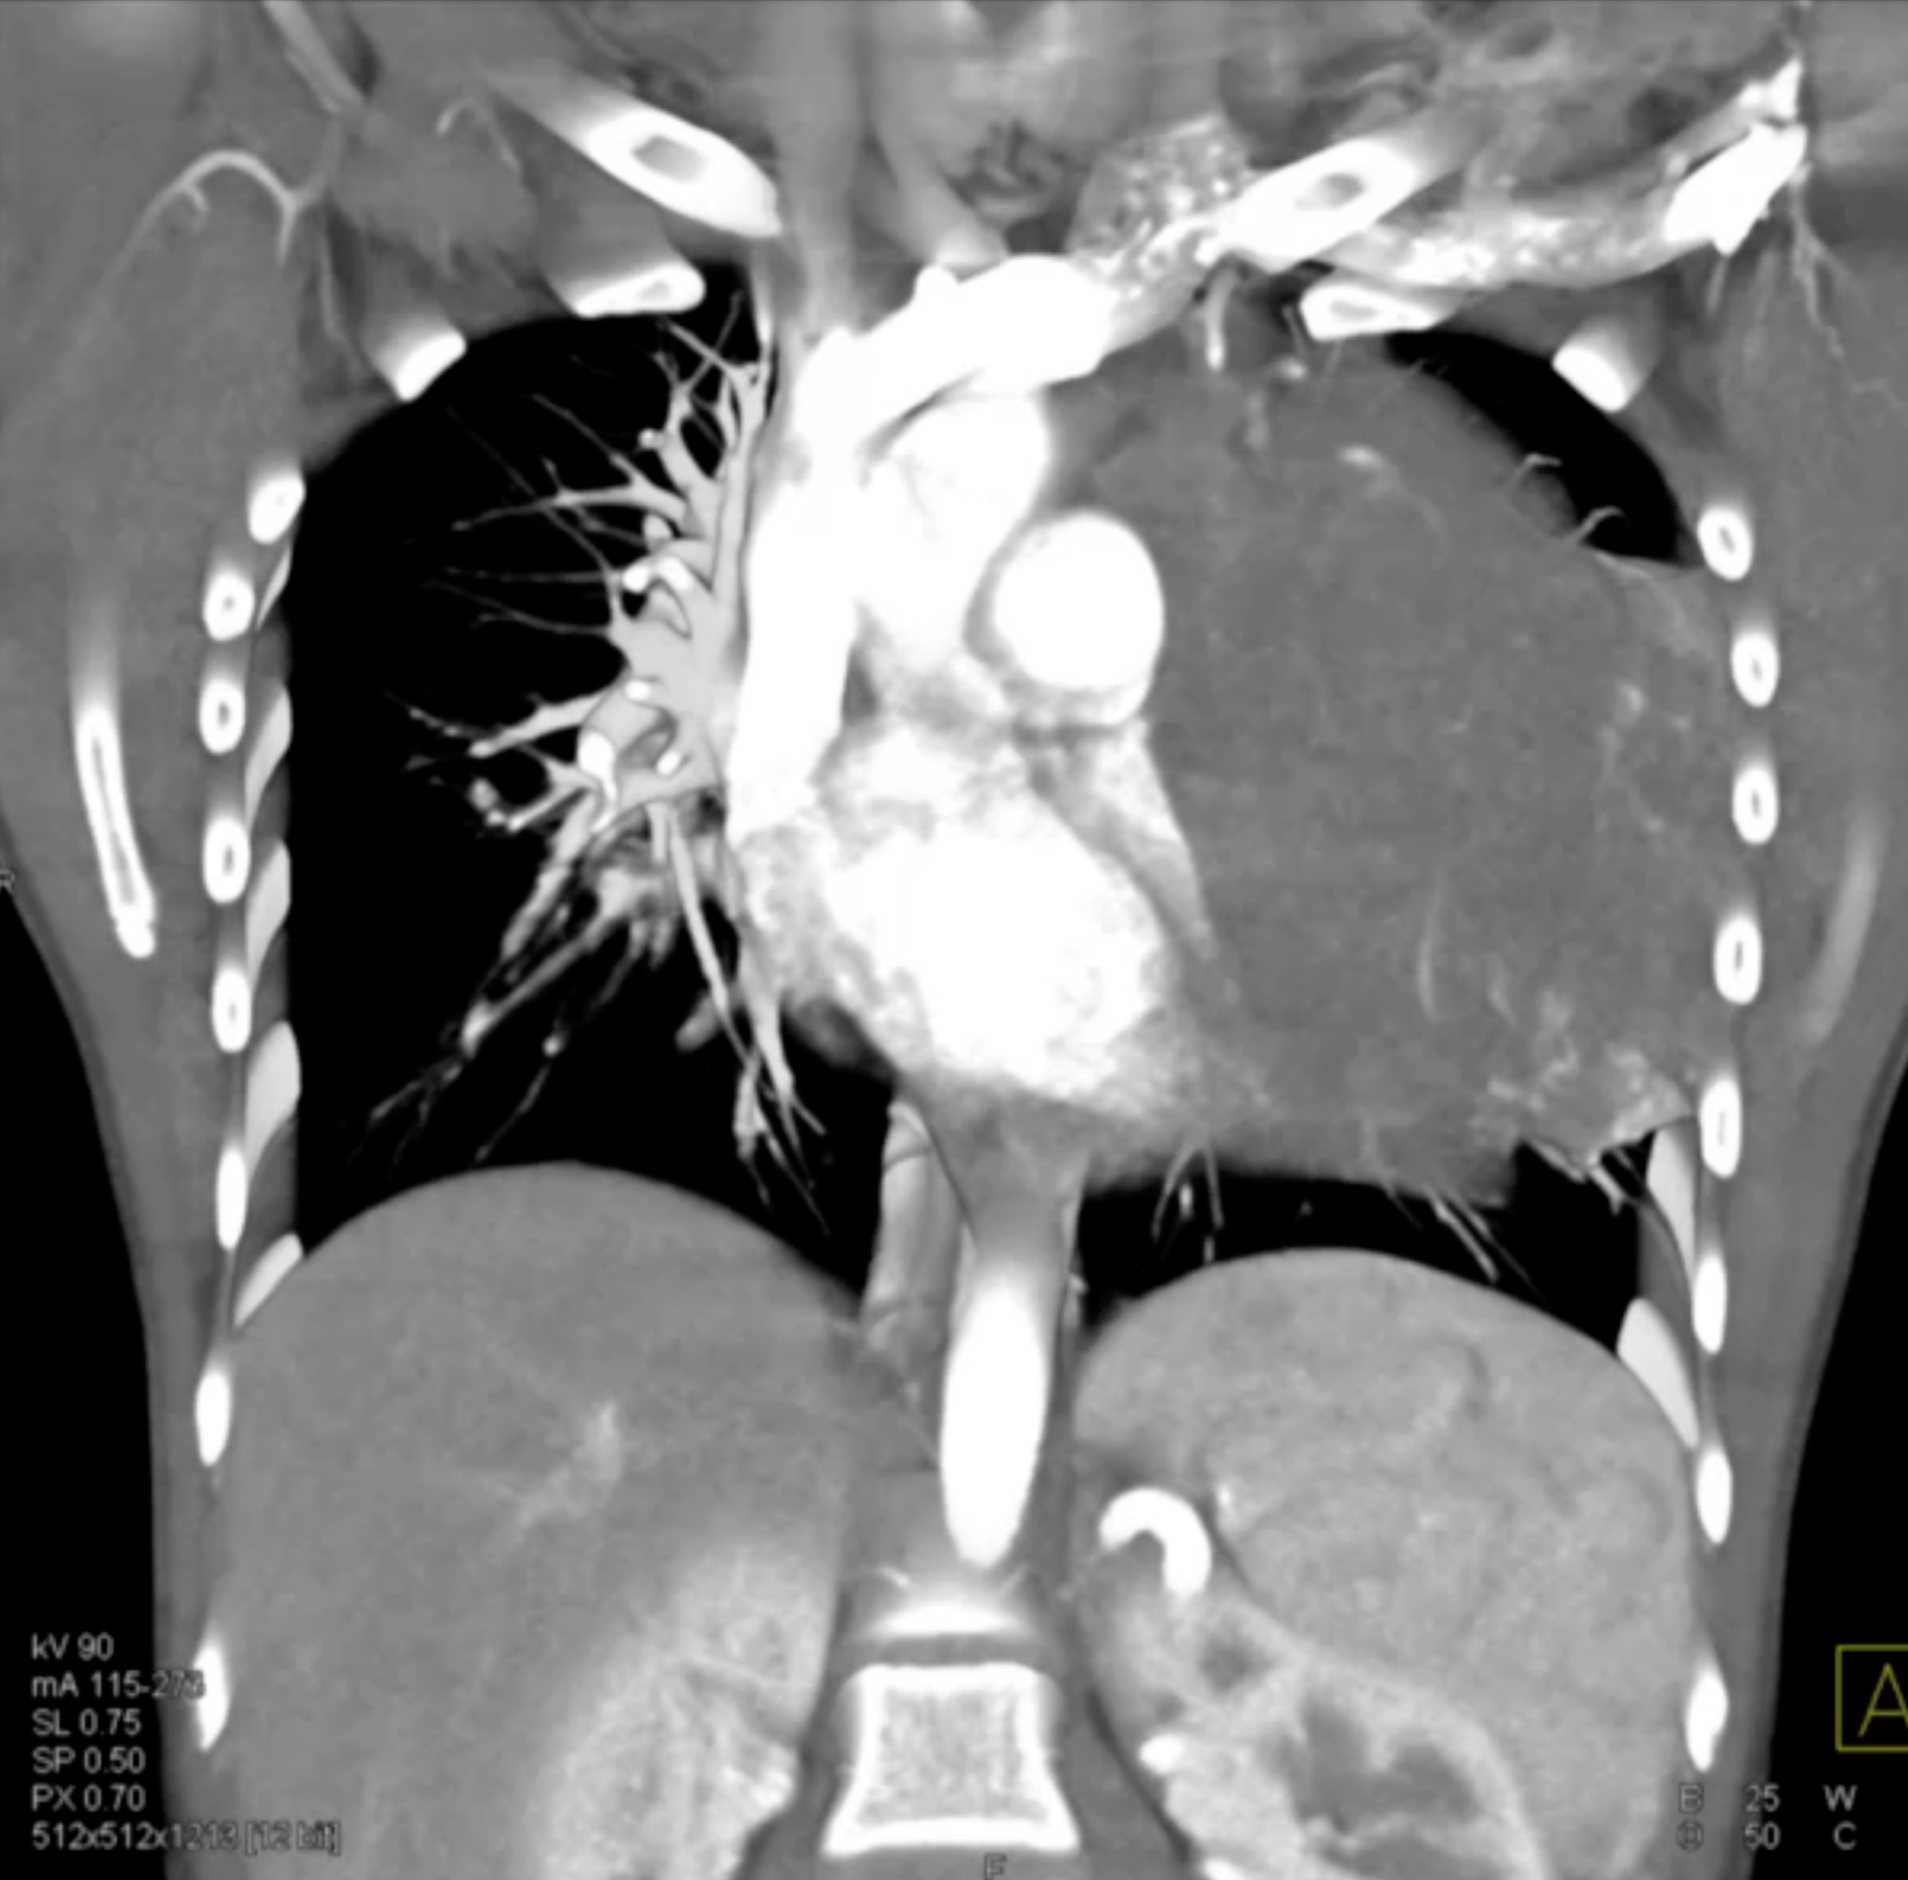

Subtle Adenocarcinoma Pancreas